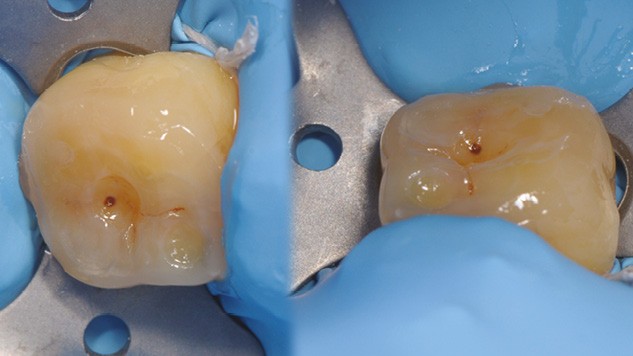

à ces restaurations correspond aujourd’hui toute une série de nouveaux design postérieurs permettant une ultra-préservation tissulaire et pouvant s’inscrire, en fonction des situations cliniques, dans l’émail (situation idéale), dans la dentine, dans le composite de base intermédiaire, ou un « mix » de ces différents supports (fig. 10 à 13).

Les épaisseurs de préparation varient donc selon la nature du support. De 0,6 à 1 mm d’épaisseur sur l’émail jusqu’à 1,5 mm sur la dentine ou le composite afin d’être en adéquation avec les modules d’élasticité des matériaux de restauration utilisés (céramique ou composite).